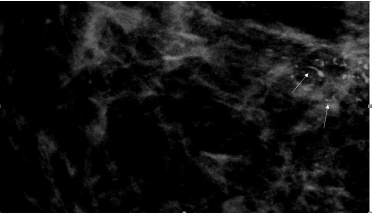

Linear and fine linear branching

As the name suggests they are fine, linear, thin, and irregular measuring < 0.5mm. They appear sometimes as discontinuous calcifications, as well as in a branching pattern, developing due to the filling in of the lumen of a duct/ducts which are involved by carcinoma. They have the highest positive predictive value amongst the suspicious calcifications (70%). They are categorised as BIRADS 4C [5]; (Figure 15).

Figure 15:RCC view of a 61-year-old woman showing linear calcifications (long arrows). Image Courtesy: HCG Hospitals, Bangalore.